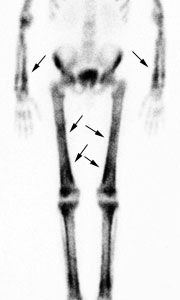

Hypertrophic osteoarthropathy: The patient shown below was being evaluated for bone pain. The bone scan revealed patchy, linear tracer uptake along the femurs, tibias, and distal upper extremitis (black arrows). A plain film reveal a solid periosteal reaction. CXR demonstrated a large right lung mass. |